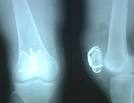

[影像学表现]

髌骨内可见横断或星形的X线透亮的骨折线,由于股四头肌腱和髌腱的牵扯,骨折块分离多较明显,骨折上段向上移位,而下段无移位。如股四头肌腱没有完全断裂,骨折移位较少见。

骨折后关节内大量积血,髌前皮下瘀血、肿胀,严重者皮肤可发生水疱。有移位的骨折,可触及骨折线间隙。髌骨正侧位 X 线可确诊。对可疑髌骨纵行或边缘骨折,须拍轴位片证实。